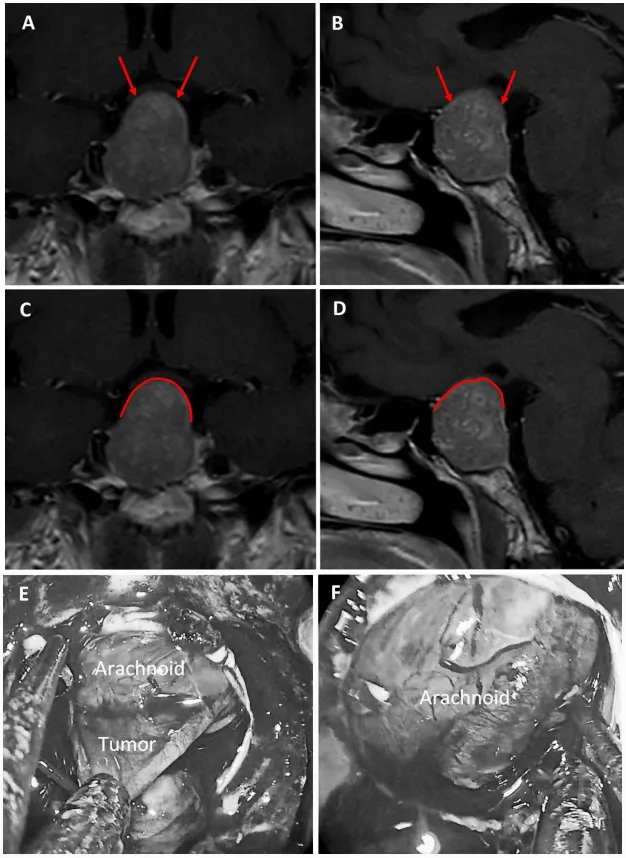

图3:67岁女性无功能大腺瘤患者。a、b术前MRI:黄色箭头指示厚度大于1毫米的强化屏障区。c、d术前MRI:黄色标记线标示强韧屏障位置。e、f术中图像:可见由硬脑膜构成的屏障结构。

图4:47岁男性生长激素腺瘤患者。a、b术前MRI:黄色箭头指示厚度大于1毫米的强化屏障区。c、d术前MRI:黄色标记线标示强韧屏障位置。e、f术中图像:可见由垂体腺构成的屏障结构。